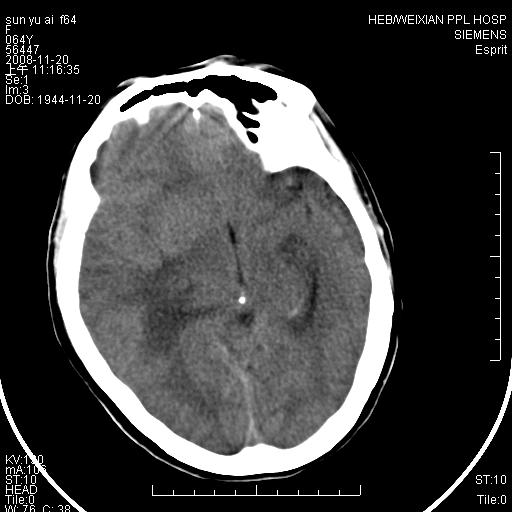

标题: CT16778:F64Y,颅内囊性占位 [打印本页]

标题: CT16778:F64Y,颅内囊性占位

影像表现:侧脑室三角区附近可见以形态不规则的囊实性肿块,其中以囊性成分为主,实性成分为辅,边缘清晰,未见水肿,轻度占位效应,脉络丛钙化向内上移位,右侧脑室轻度扩大(也许体位所致),

影像诊断:1室管膜瘤

2胆脂瘤 建议增强吧

1、右侧大脑半球囊实性占位病变,以囊性变为主,实性部分位于病变外后侧,周围无明显水肿,占位征象明显。

2、多考虑胶质瘤可能性大。